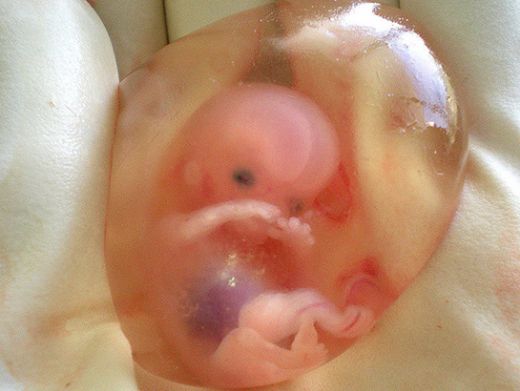

7 Haftalık Gebelikte (Hamilelikte) Kanama Nedenleri?

3 Aylık Gebelikte (Hamilelikte) Kanama Nedenleri?